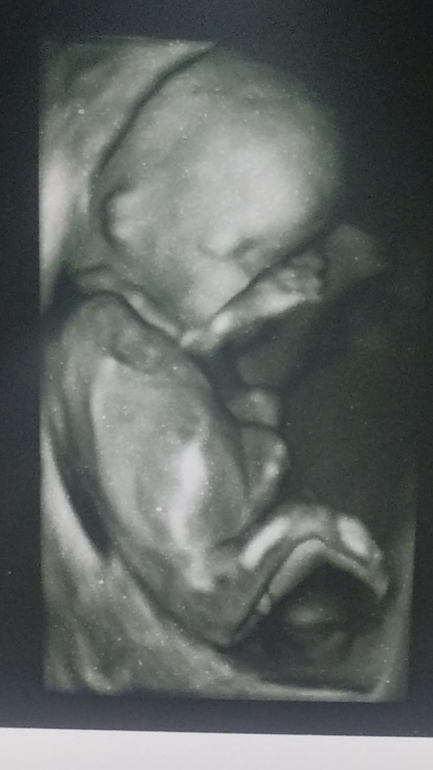

Половой бугорок!!!)))

Вопрос про половой бугорок ))))))

(По нему же предполагают пол ребенка на маленьком сроке)

УЗИстка предположила, что скорее всего девочка.

Если бугорок меньше 30 градусов- девочка,если больше-мальчик. Судя по всему у вас девочка)